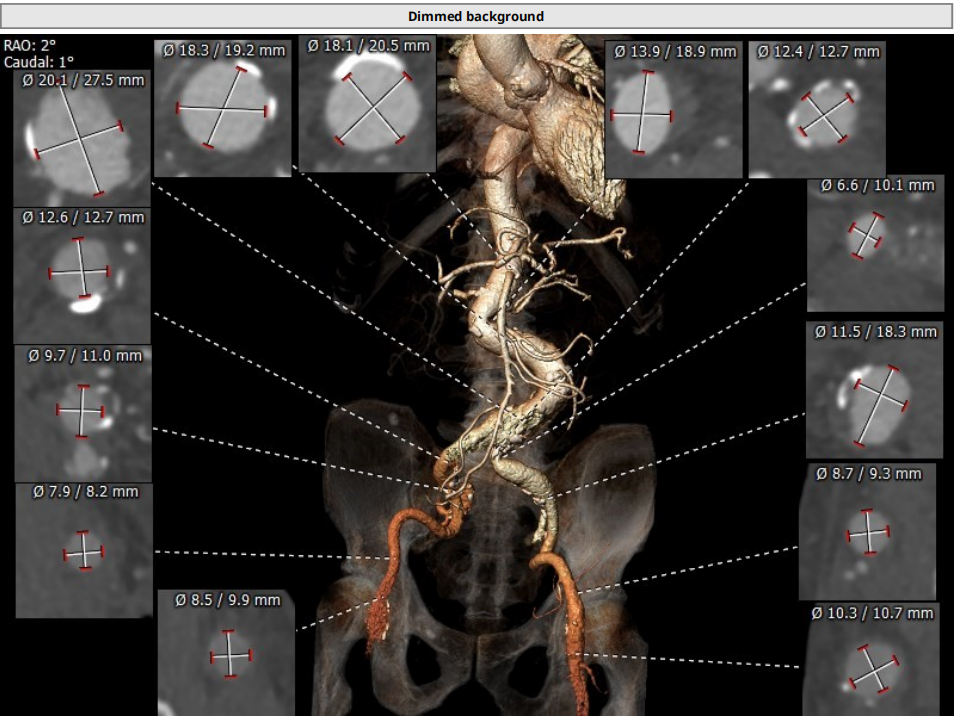

术前CT结果显示,主动脉瓣极重度钙化;主动脉瓣口面积562.8mm²,瓣环平均直径27.4mm,瓣环周长85.6mm;LVOT面积626.9mm²,LVOT平均直径28.4 mm。CT同时显示外周入路血管重度扭曲合并右侧腹主动脉瘤样病变。

图2 术前CT影像评估结果